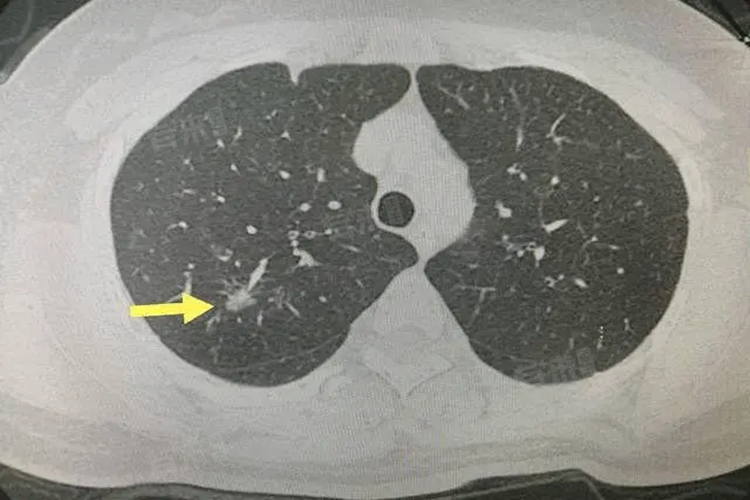

- 恶性肺结节如肺癌引起的结节,在增强CT上往往有不均匀强化的特点,是因为肿瘤组织内部血管分布杂乱,新生血管的结构和功能异常,导致造影剂在肿瘤内的分布不均匀。恶性结节的边缘常常不规则,有毛刺征、分叶征等表现,毛刺征是由于肿瘤细胞向周围组织浸润生长,刺激周围的纤维组织增生所形成;分叶征则与肿瘤各部分生长速度不同有关。